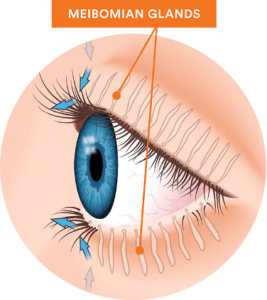

It treats dry eyes by improving the function of the meibomian (oil) glands of the eyelids. Meibomian glands that are not functioning properly can eventually lead to gland dropout (loss) or atrophy, which leads to long-term and severe dry eye symptoms. When meibomian glands don’t secrete enough oil onto the eye, tears evaporate too quickly, leading to a cycle of inflammation.

It treats dry eyes by improving the function of the meibomian (oil) glands of the eyelids. Meibomian glands that are not functioning properly can eventually lead to gland dropout (loss) or atrophy, which leads to long-term and severe dry eye symptoms. When meibomian glands don’t secrete enough oil onto the eye, tears evaporate too quickly, leading to a cycle of inflammation.

This leads to dry eye symptoms such as burning sensation, stinging, irritation, tearing, and redness. By restoring gland function, IRPL can make sure your eyes have the proper hydration.

IRPL produces perfectly calibrated light pulses that target the meibomian glands. These light pulses result in a neurological stimulation of the parasympathetic nerve which supplies the meibomian glands.

This neurological stimulation helps to:

The regulated light pulses from IRPL help break the vicious cycle of inflammation, leading to a long-term improvement of dry eye symptoms. It also helps prevent further atrophy of the meibomian glands.